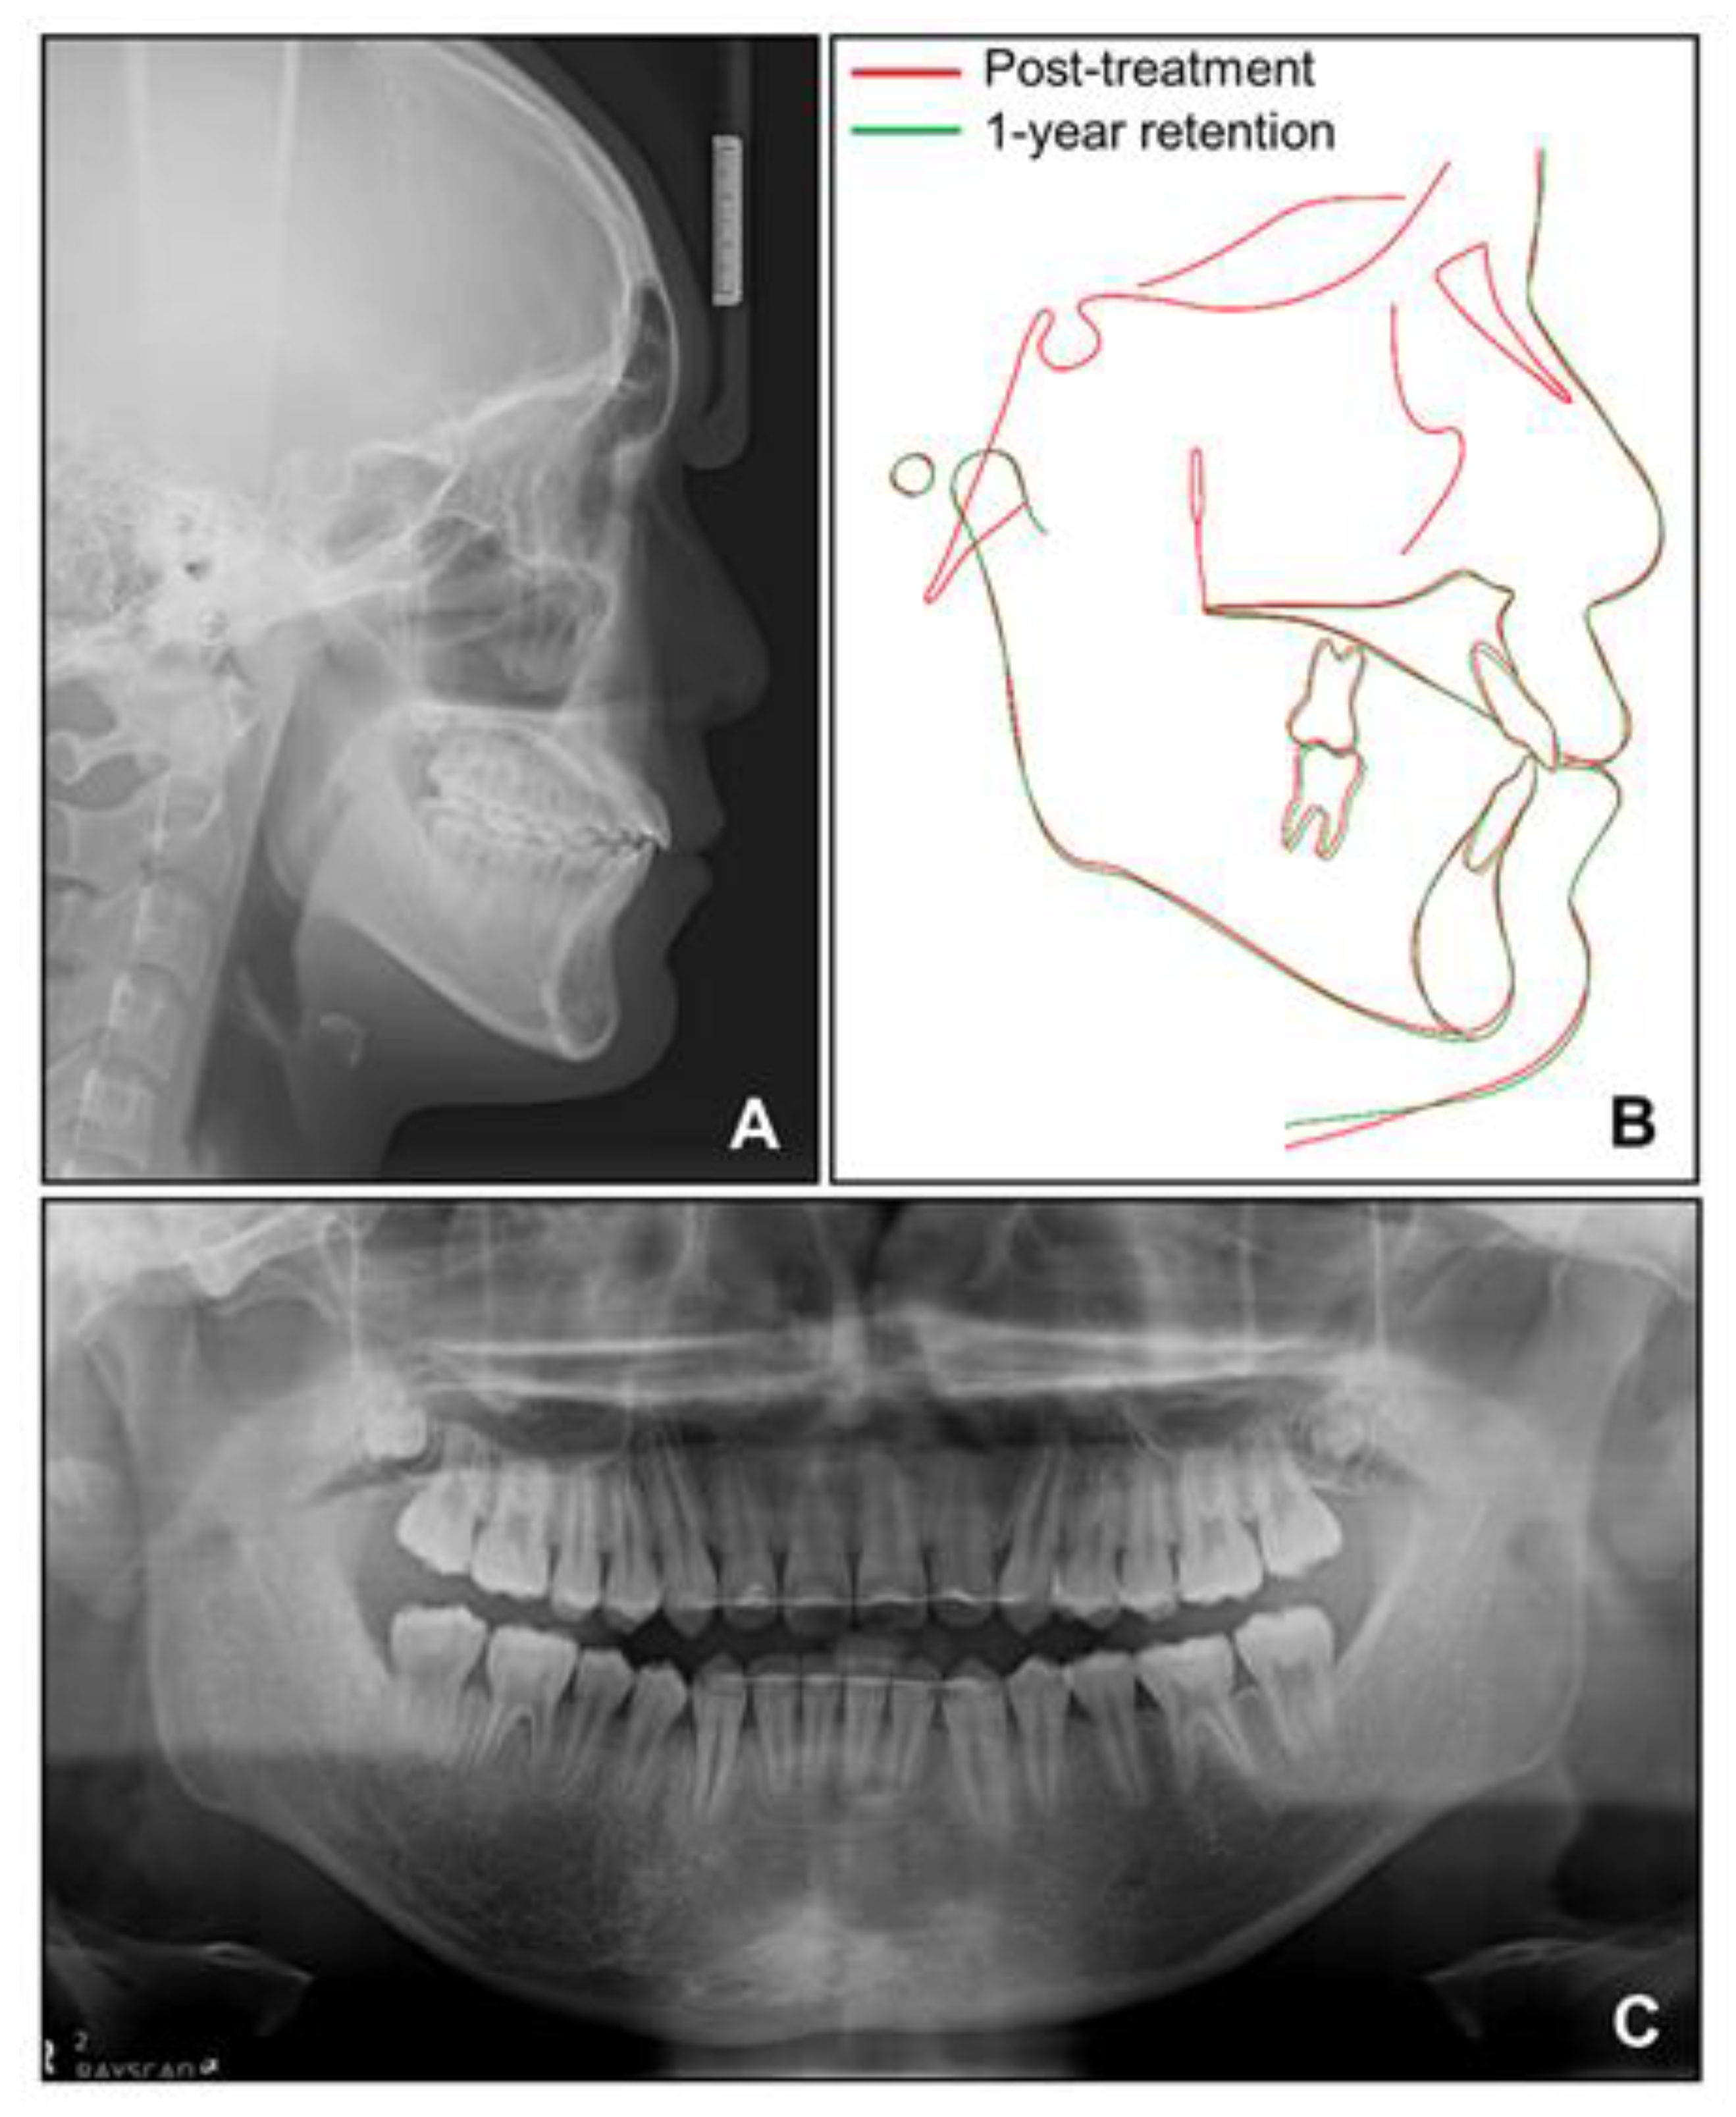

Figure 14. Radiographs for 1-year retention. (A) Lateral cephalogram; (B) Superimposition between post-treatment and 1-year retention; (C) Panoramic radiograph.

Cephalometric analysis showed that a skeletal Class I relationship was well-maintained after the phase 1 treatment, with an ANB of 2.5°. Both previously lingually inclined maxillary and mandibular incisors were improved to the normal range. The patient was satisfied with the results and remained stable for 1 year after debonding. While a slight relapse pattern of open bite was observed in the left anterior region, no remarkable increase in the right mandibular right hypertrophic region was observed (Figure 13 and Figure 14).

During the intrusion of the mandibular anterior teeth into the hypertrophic alveolar bone area in the anterior right mandible, we carefully monitored the patient to avoid side effects. Fortunately, he showed neither a loss of periodontal attachment nor root resorption of the mandibular anterior teeth after intrusion. Surprisingly, the size of the hypertrophic area diminished after orthodontic treatment and remained stable until the latest follow-up at 1 year after debonding. However, we observed an open bite at the left mandibular anterior area 1 year after debonding. During the segmental intrusion of the mandibular anterior teeth, intrusive force was applied to the right segment, and consequently, extrusion occurred at the left segment, which might have contributed to the relapse of the left anterior open bite. If the open bite tendency had been due to a progressive increase in the hypertrophic area, there would have been an open bite tendency in the posterior area as well. In addition, since a posteroanterior cephalogram was not taken after the phase 1 treatment in this case, the degree of change in the facial asymmetry of the patient during the phase 1 and phase 2 treatments could not be quantitatively confirmed through superimposition. Since orthodontic treatments in cases such as this are few, periodic follow-up and long-term monitoring are required in this case.